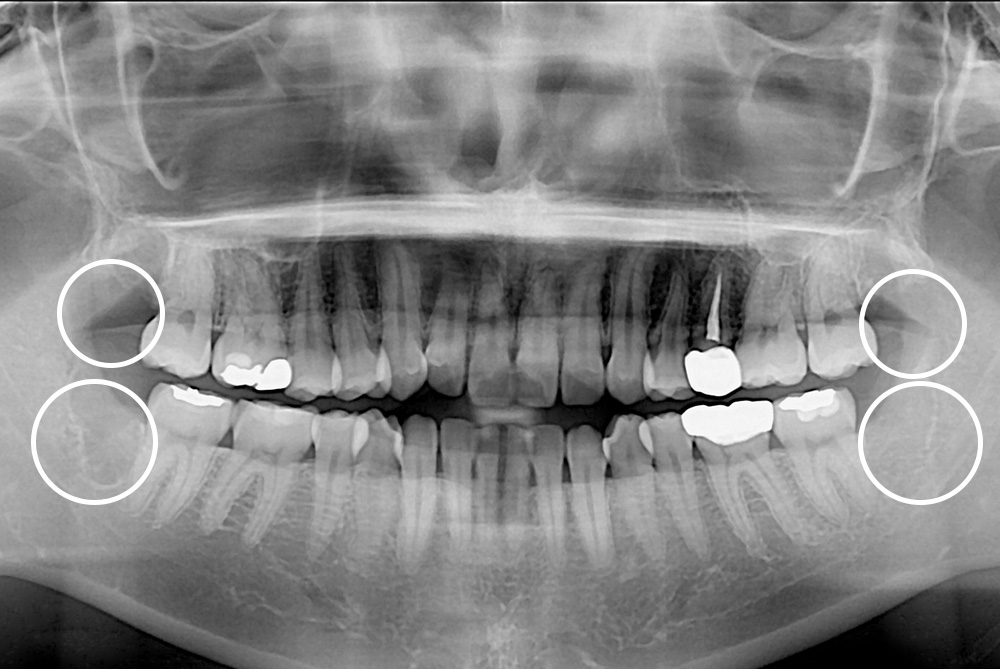

[사랑니] 매복 사랑니 발치

치료후 : 2018-12-03

세종치과는 구강악안면외과학 박사이신 원장님이 발치하는 치과입니다.